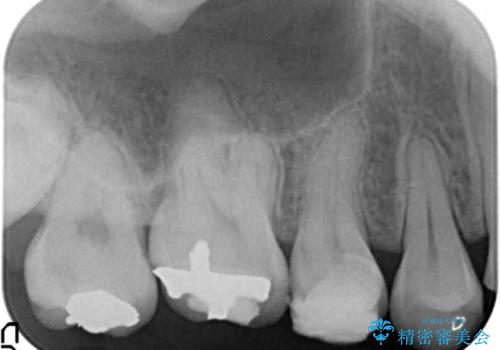

- K-POP(Kポップ)アイドルのような歯にしたいと希望され来院された患者様です。

矯正を途中でやめてしまったとのことで、歯に矯正の接着材が残っており着色も顕著でした。

奥歯の咬合面にはレジンが盛られた状態でした。

見た目と咬み合わせを改善するため、セラミッククラウンによる治療を行いました。